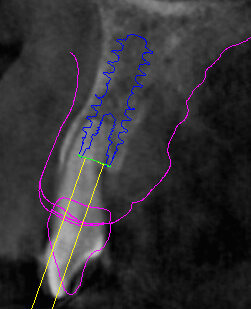

Il piano di trattamento prevede l’estrazione degli elementi dentali, l’inserimento di due impianti e la realizzazione di una protesi fissa di quattro elementi. Il problema da gestire è quello della fase provvisoria. Non è ipotizzabile una protesi mobile e quindi programmiamo di inserire subito dopo l’intervento un provvisorio immediato. Questo ci consente di condizionare da subito i tessuti periimplantari e anche le zone dei ponti. Si rileva un’impronta digitale (Figg. 5, 6), e la programmazione degli impianti viene effettuata con un software di chirurgia guidata (Fig. 7) e la posizione degli impianti nello spazio biologico e nello spazio protesico viene fatta sulla base di una ceratura diagnostica (Figg. 8, 9). Inseriamo gli impianti virtuali nell’osso disponibile (Figg. 10-13) e in relazione all’aspetto protesico correggiamo l’asse di inclinazione degli impianti con componenti secondarie angolate a 17° (Figg. 14, 15). Questo ci consentirà di realizzare una protesi avvitata con i fori situati nella zona palatale.

Fig. 11 - Posizionamento virtuale dell’impianto 2.2.

Fig. 13 - Cross impianto 2.2.